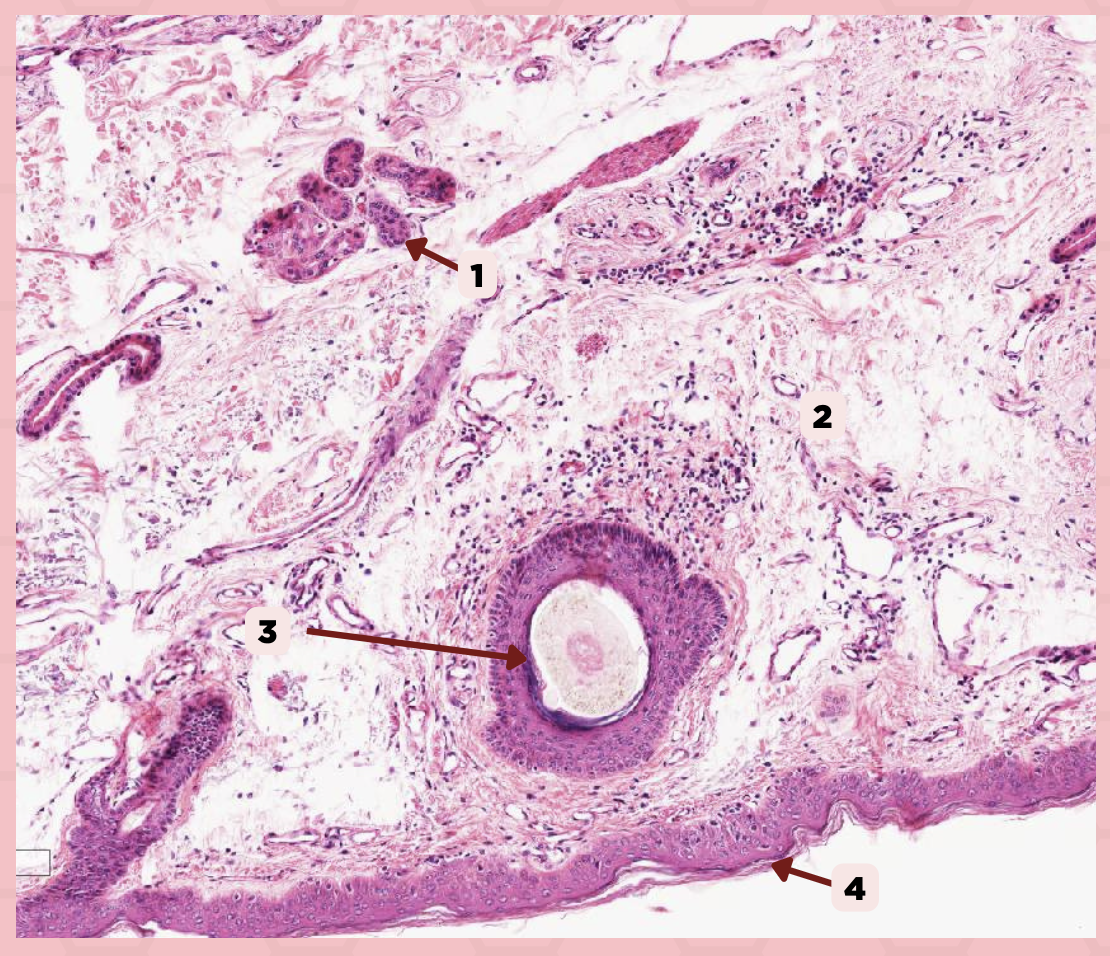

Lip

What specimen is being showed in the picture?

Epidermis

Identify the structure labeled as 1.

Dermis

Identify the structure labeled as 2.

Arrector Pilli Muscle

Identify the structure labeled as 3.

Hair Follicle

Identify the structure labeled as 4.

Sebaceous Glands

Identify the structure labeled as 5.

Lip

What is the specimen showed in the picture?

Epidermis

Identify the structure labeled as 1.

Dermis

Identify the structure labeled as 2.

Arrector Pilli Muscle

Identify the structure labeled as 3.

Hair Follicle

Identify the structure labeled as 4.

Sebaceous Glands

Identify the structure labeled as 5.